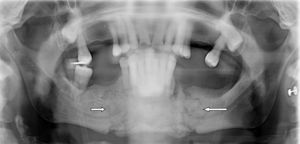

In 2015, with no other precipitating factors (for example oral surgery), active intraoral discharge was clinically detected and exposure of the intraoral necrotic bone. Panoramic radiograph was performed which showed bilateral mandibular non displaced fracture (Fig. 1). At the moment, following antibiotic treatment with amoxicillin 1g/8h and daily mouth rinses every 8h with 2% chlorhexidine, clinical evolution has been stable, without any fragment displacement that requires surgery.